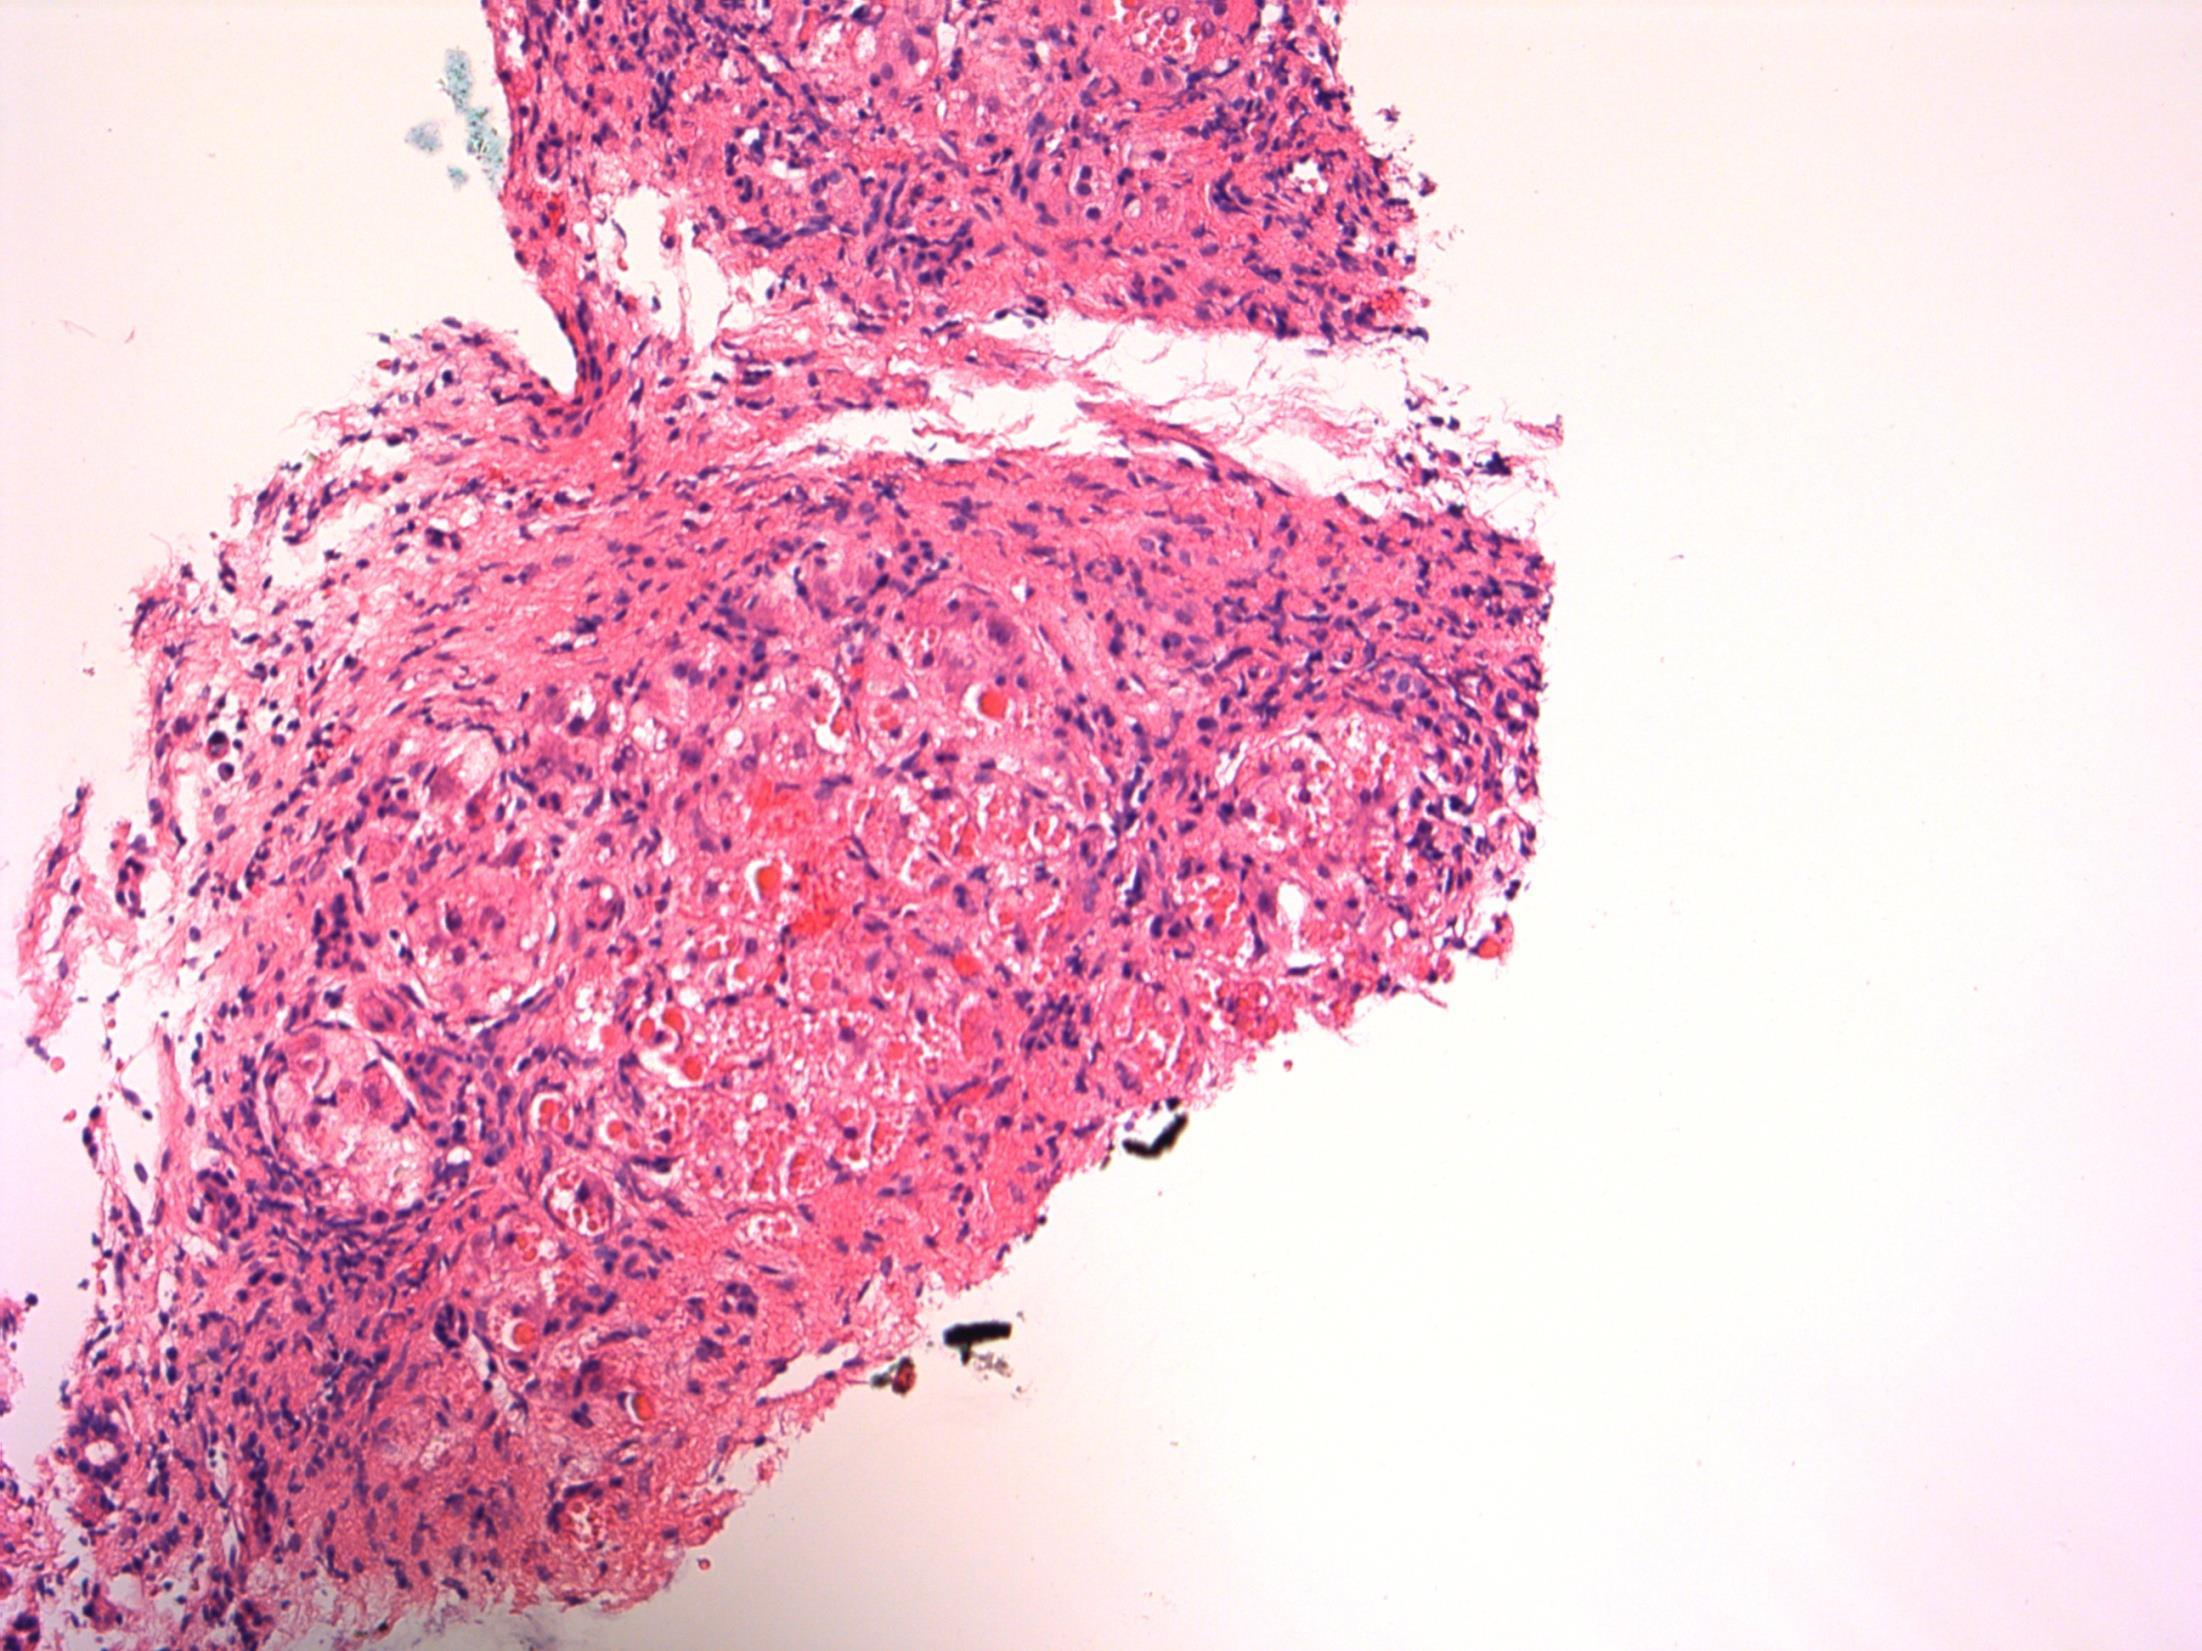

24F, Intensely itchy, excoriated papulovesicles over knees, left elbow and sacrum. Biopsy from right knee lesion. DIF from adjacent skin: Granular deposits of IgA in dermal papillae.

• Skin – Dermatitis herpetiformis

Description: Acantholytic dermatosis. Subepidermal blisters with neutrophils, oedema in papillary dermis. No evidence of malignancy.

Diagnosis: Dermatitis herpetiformis

• Linear IgA dermatosis – Children; Similar histology, DIF- IgA linear rather than granular.

• Bullous pemphigoid – Blister lumen and dermis are rich in eosinophils and neutrophils; DIF – linear deposits of IgG, C3 and IgA (40%) at DE junction.

Comments: Autoimmune– IgA against epidermal transglutanimase, association with gluten sensitive enteropathy. Does this patient have any history of coeliac disease?

Typical clinical features -excoriated, grouped papulovesicles on knee, elbow, sacrum, as described in this clinical history. DIF – Granular deposits of IgA in papillary dermis and D-E junction as described for this patient.

3.5 Pathogenesis, associations 3.0 Differential diagnosis and use of DIF 2.5 Description with diagnosis 2.0 Other benign diagnosis with mention of DH 1.5 Other diagnosis with no mention of DH 1.0 Malignant diagnosis